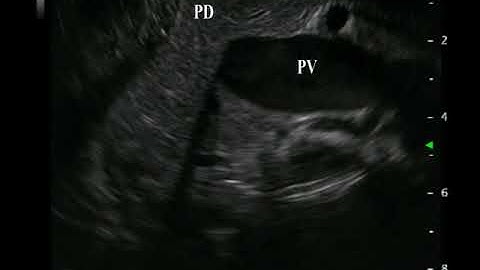

Video 19 Scanning Ampulla and Papilla from Duodenum